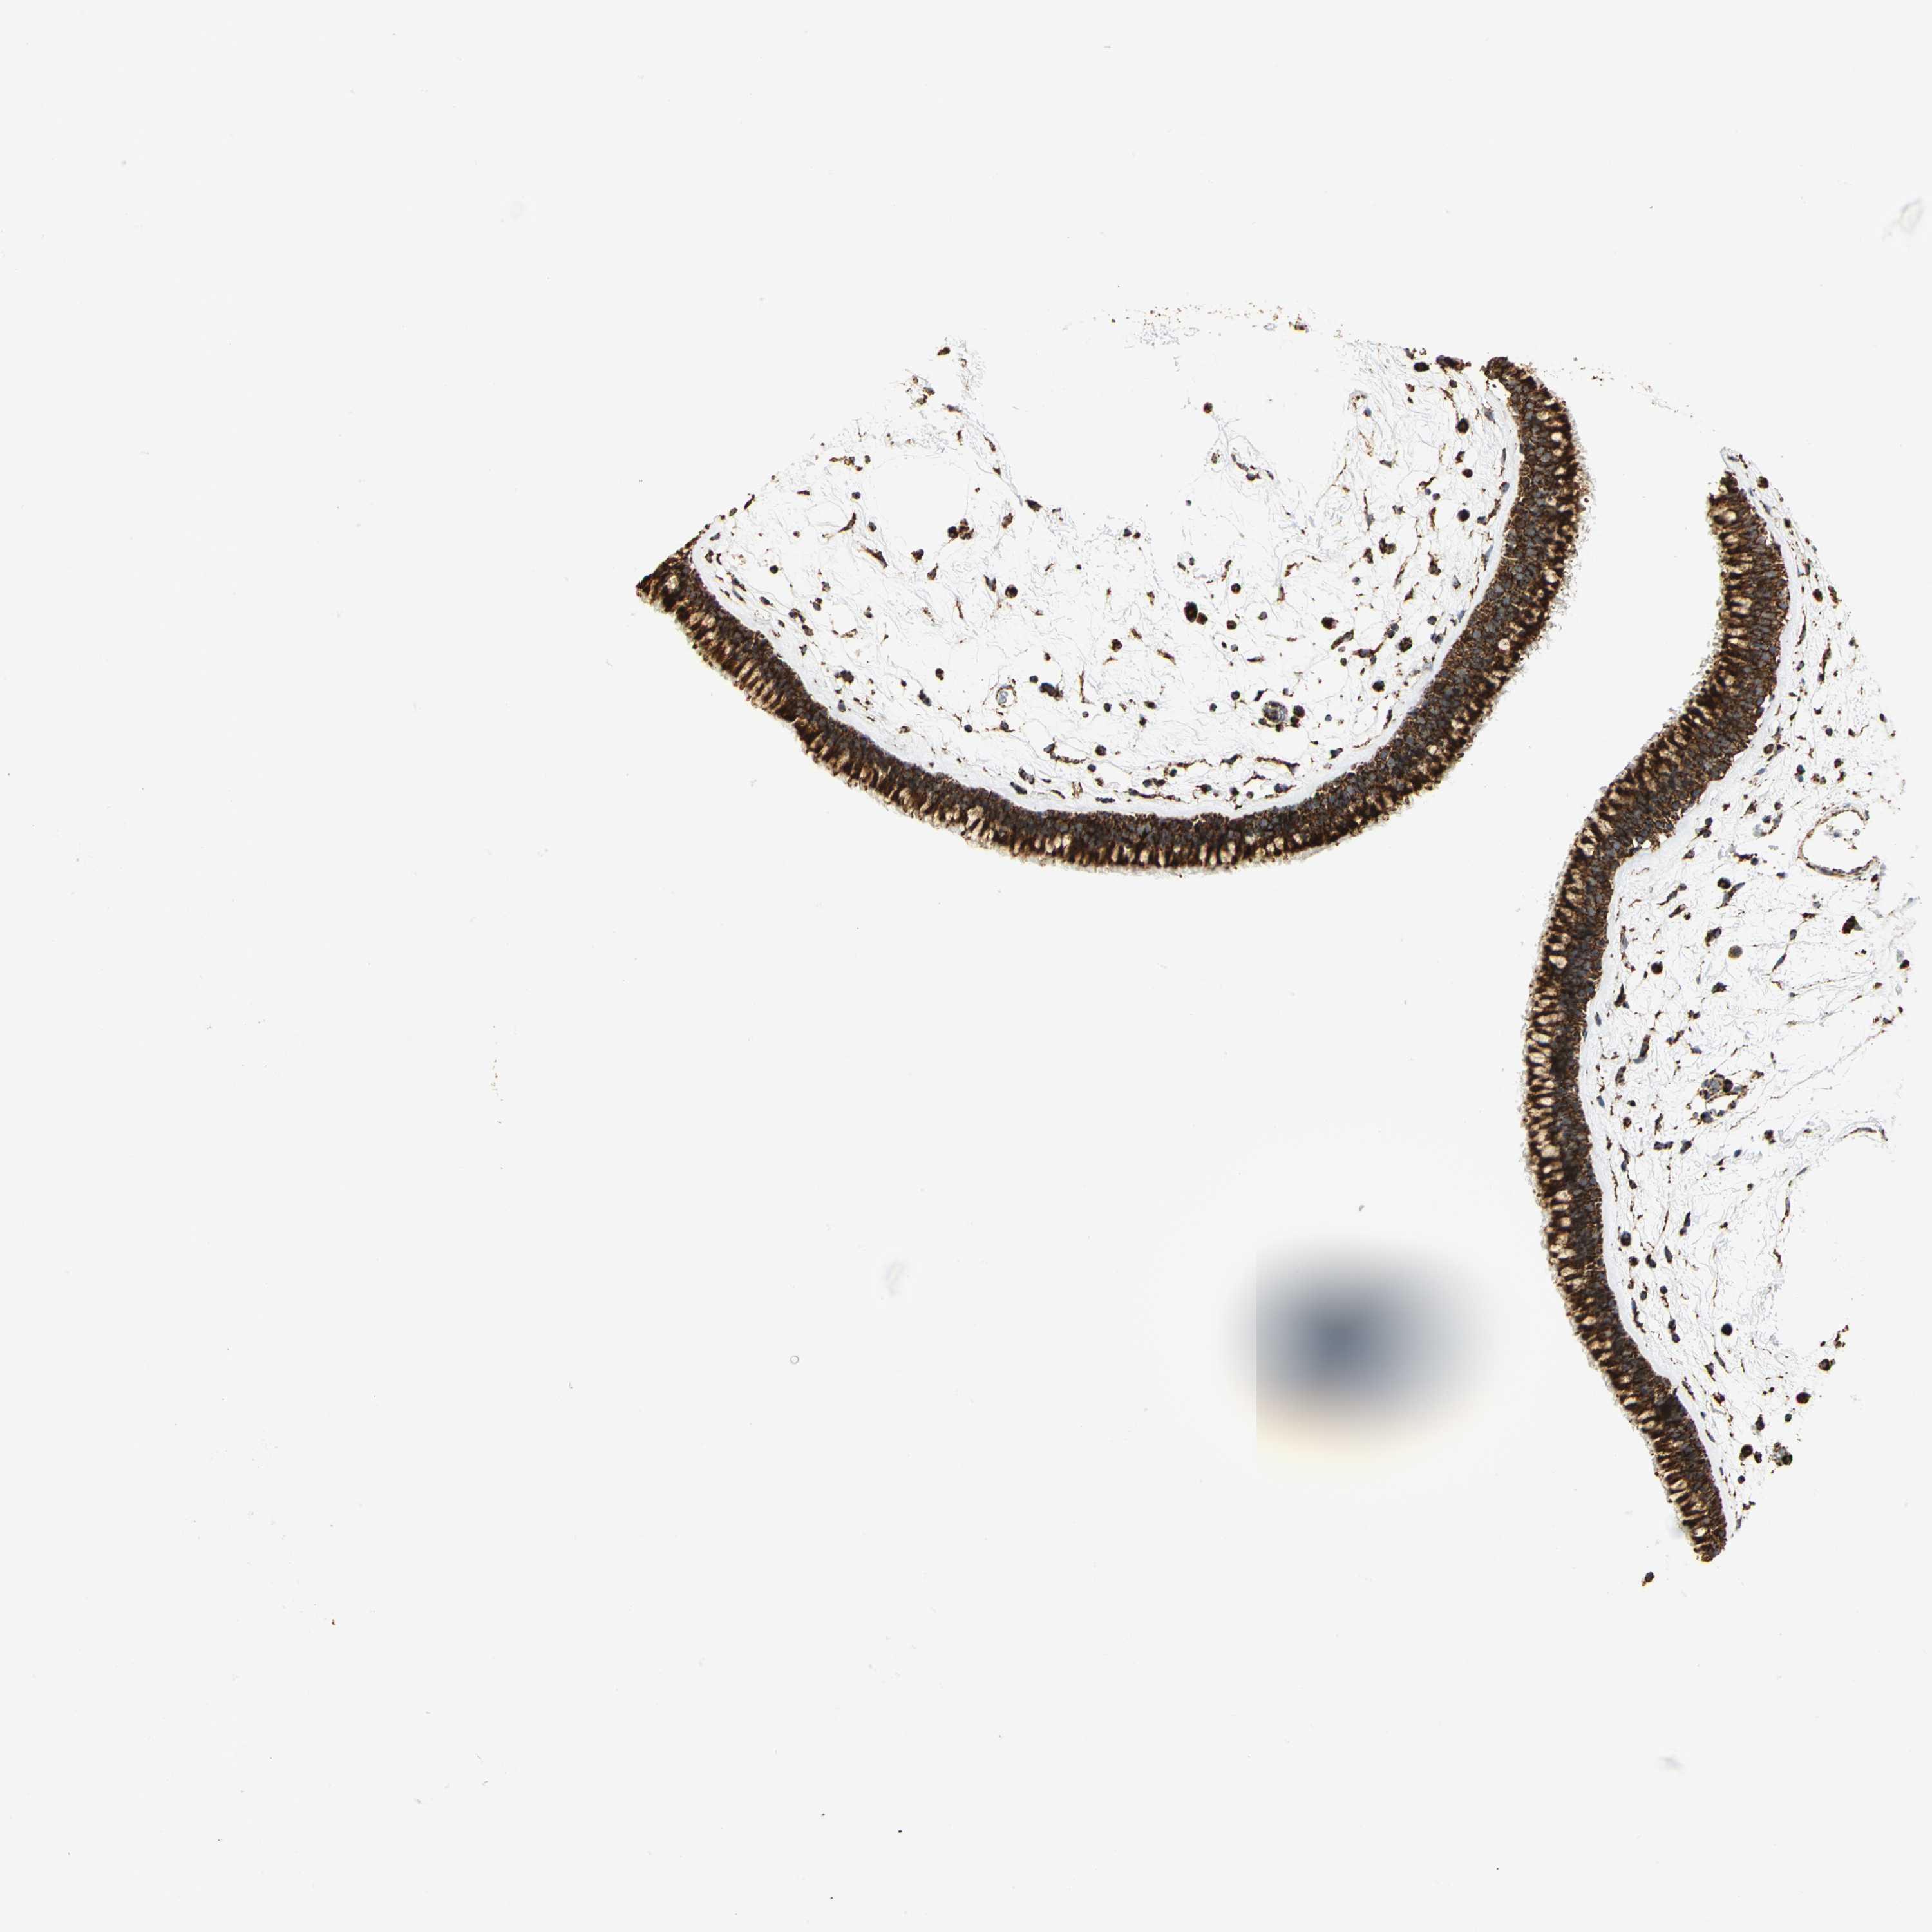

NASOPHARYNX - Antibody stainingi

Antibody staining in the annotated cell types in the current human tissue is reported as not detected, low, medium, or high, based on conventional immunohistochemistry profiling in selected tissues. This score is based on the combination of the staining intensity and fraction of stained cells.

Each image is clickable and will lead to virtual microscopy that enables deeper exploration of all samples and also displays staining intensity scores, fraction scores and subcellular localization as well as patient and tissue information for each sample.

Antibody HPA030780Antibody CAB005885Antibody CAB072343

Respiratory epithelial cells HighHighHigh